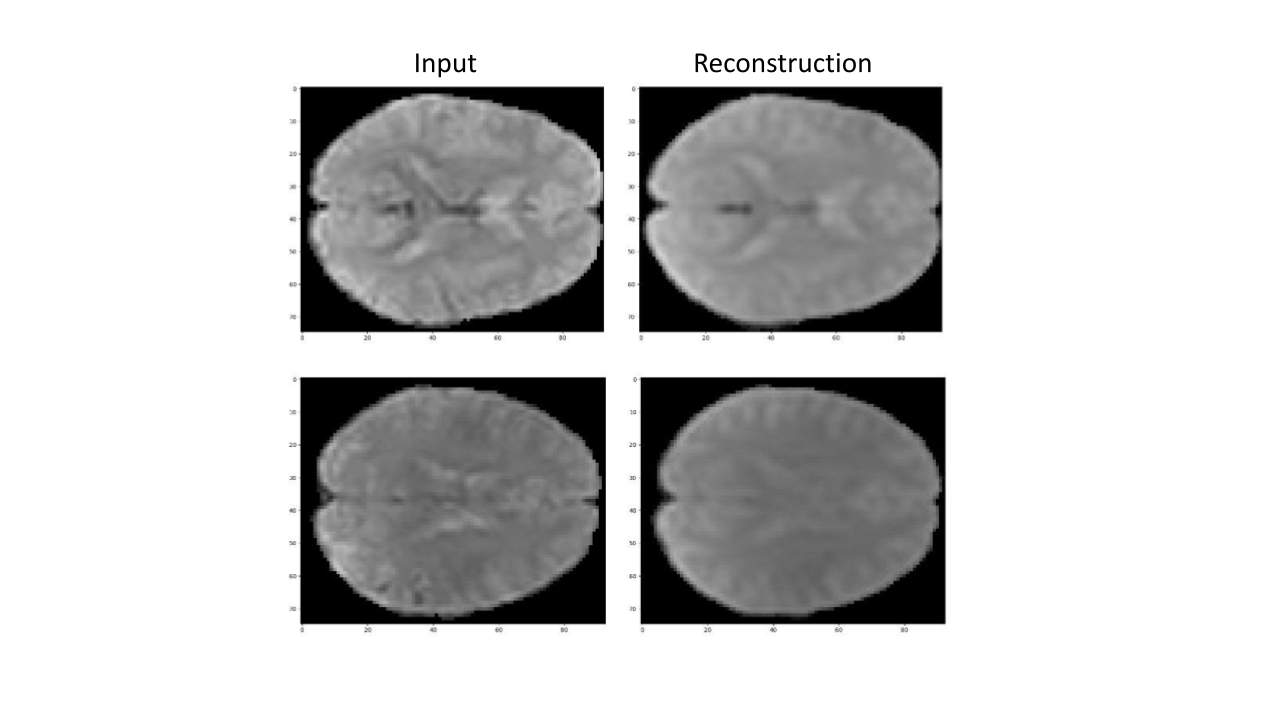

blackFig. 5 presents two slices fron two representative fMRI scans (from the validation set) that were encoded and decoded by the pre-trained TFF model. As can be seen, TFF is able to preserve most of the information from the input, including the brighter areas which indicate a higher level of brain activity. This ability of the model to accurately reconstruct the volumes is an important indication for the quality of the intermediate vectors, and the sanity of the end-to-end training.